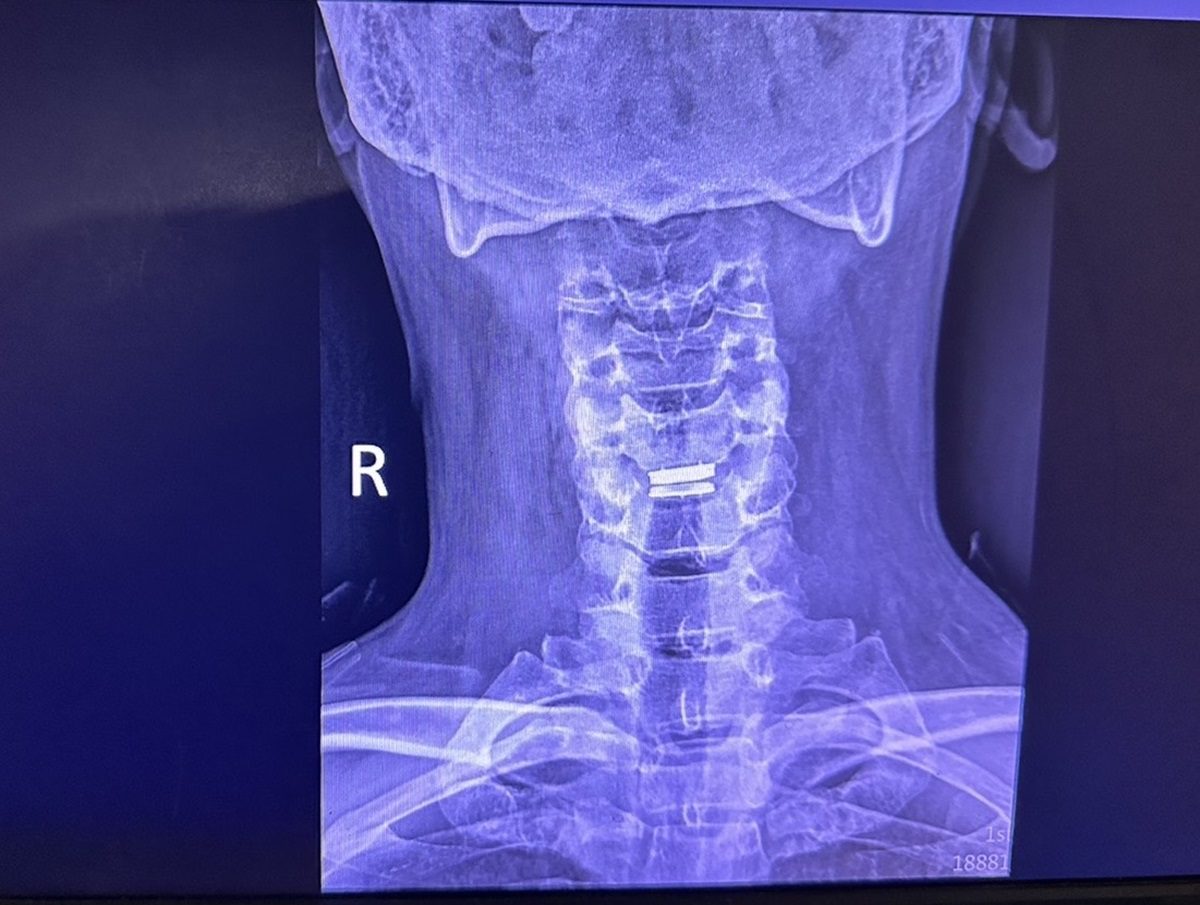

彰化秀傳紀念醫院神經外科首席主任鄭均洹分享,有一位打火弟兄在一次執勤後出現頸椎疼痛,隨後痛感逐漸延伸至左手臂;雖然他進行了藥物與復健治療,但症狀未見改善,反而更加嚴重。經神經外科門診診斷及核磁共振檢查顯示,他罹患頸椎椎間盤突出,壓迫到頸椎神經根。最終,該消防員接受了頸椎椎間盤切除及人工椎間盤植入手術,術後狀況明顯改善,預計三個月後即可重返工作崗位。

▲打火弟兄罹患頸椎椎間盤突出,壓迫到頸椎神經根。(圖/記者蕭麗鳳攝)

▲如果壓迫過於嚴重,則可能需要進行手術來減壓。(圖/記者蕭麗鳳攝)